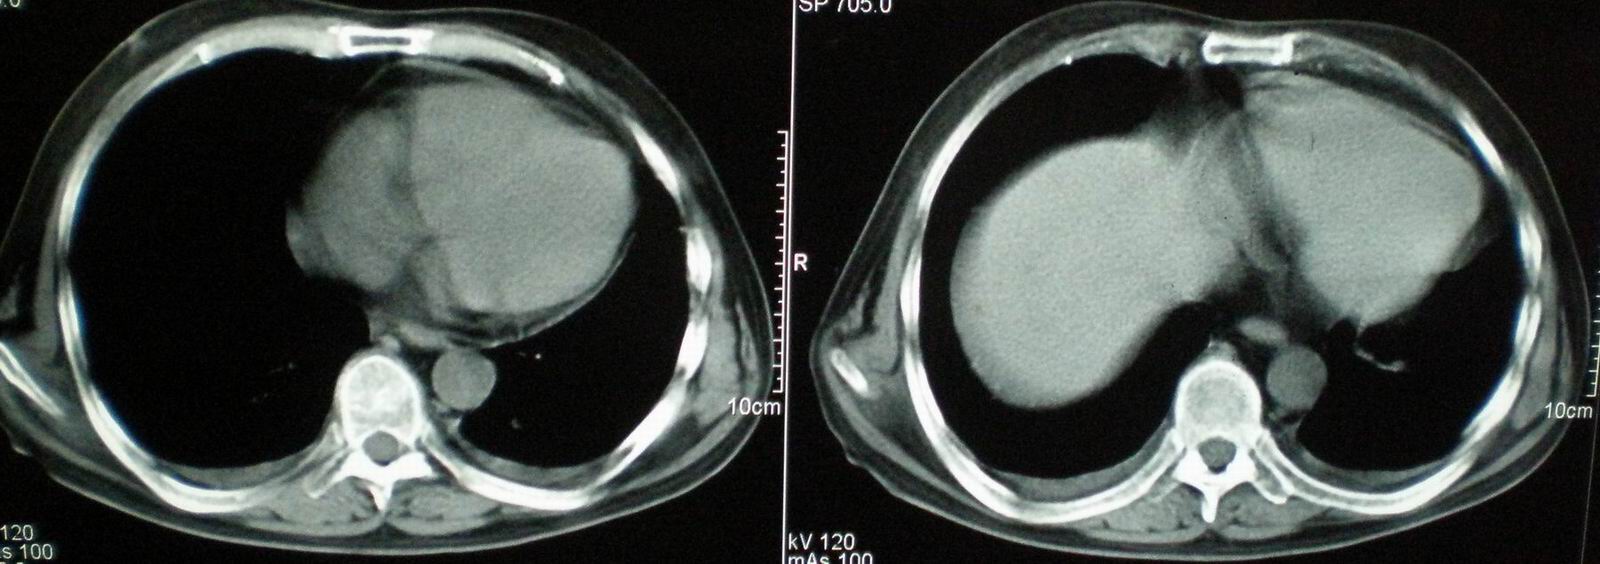

2008年11月18日今天的ct片

2008年9月18日ct片

2008年9月8日ct片:

[face=宋体]显然上级医院进行了抗结核,抗真菌,抗炎等治疗,目前病人肺内病灶基本消失,双侧胸腔积液,右侧积液量有吸收,抗结核一个多月,现在病人疑问,结核的诊断是否有疑义,抗结核是否继续,因为那个毕竟副作用大。[/face]

我仔细看了下病人的出院小结,当时情况危急,诊断里有1型呼衰。心包周围的是脂肪密度。结合三次ct扫描的图象分析,个人认为:1、病人目前肺部病灶基本消失,双侧胸腔内少量积液,抗结核治疗才一个多月,就算是结核,抗结核治疗有效果,为何效果如此好,一点纤维灶的痕迹都没有呢,再就是患者做过气管镜检查及活检、痰检均未找到结核的证据。所以不支持结核的诊断。

2、结合现在的ct片,考虑:肺水肿及真菌感染,双侧胸腔积液。